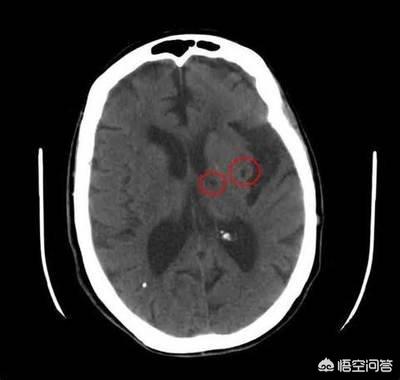

空洞性脳梗塞は、大脳半球および脳幹の深部白質に発生する虚血性微小脳梗塞である。梗塞巣は不規則な円形、卵形、または細長い形をしており、その直径は数ミリである。以前は、この現象はヒトの脳の病理解剖時にのみ検出されていた。CTやMRIが普及し、技術が進歩するにつれて、ラクナ脳梗塞が発見される確率が高くなった。

2.空洞性脳梗塞:長年の高血圧、糖尿病、高脂血症などを基盤として、脳の小動脈が加齢とともに血管壁に病変を生じ、内腔が閉塞して小さな梗塞巣が形成される疾患である。

簡単に言えば、脳梗塞は中・大動脈の閉塞の結果であり、ラクナ脳梗塞は非常に小さな動脈の閉塞の結果である。

厳密に言えば、ラクナ脳梗塞とは、大脳半球や脳幹の深部にある細い貫通動脈が、長期にわたる様々な危険因子の関与、特に高血圧の影響によって血管内腔の閉塞を起こし、小さな梗塞巣を形成したものである。例えるなら、脳を白い紙とすると、ラクナ脳梗塞は白い紙の上に撒かれたゴマで、非常に小さいがすでに存在している。